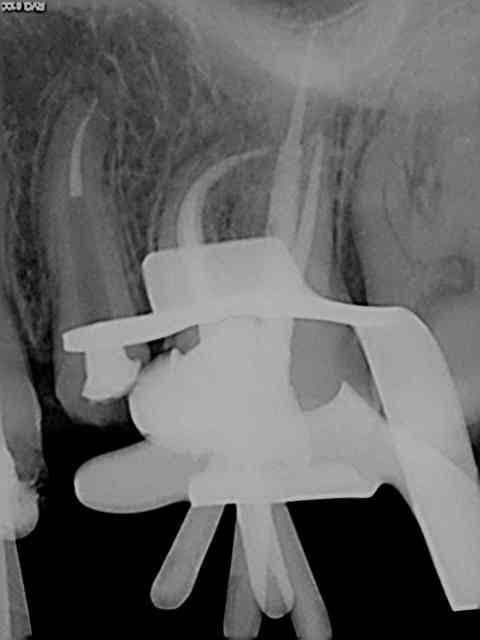

Marc tu cherches midi à 14 H. Séquence utilisée pour ces 16 et 26 (MV2 inclus) sans aide optique ni controle visuel de toutes facons tout à la "sensation". Aucun des instruments utilisés ne fait de faux canaux (largo sur double bague verte contre angle endo sur un bague bleue je ne répond plus de rien lol !)) Et je peux te dire que j'en ai essayé des systèmes ! Contrairement à ce que tu dis les s1 et S2 protaper cassent rarement ce sont les F1 ET F2 qui cassent pour un oui ou pour un non sauf évidemment si ils ne servent à rien (canal large ou déjà préparé )!))))))

SX, R25, Largo 3, SX, S1, R25, S1 (apex), R25 ( apex).